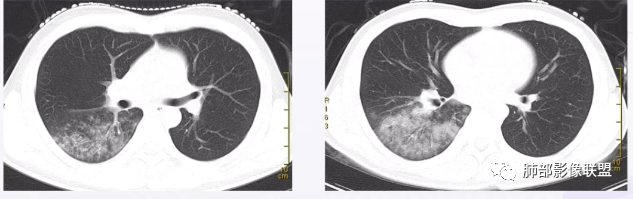

青藤之凉: 支原体肺炎的影像特征相对比较明显。有支气管壁增厚、支气管扩张样改变、支气管充气征。小叶小结节,有点状或者斑片状的浸润影、有实变影,表现为树芽征、树雾气征。

青藤之凉: 临床特点:①临床轻,影像重,病程较长。②儿童和青少年发病。

影像学特点:①支气管壁增厚、支气管周围炎。②腺泡结节、树芽征、树雾征(见病例1)。③结节融合,大片实变,部分边缘收缩。④分布上较广泛 。